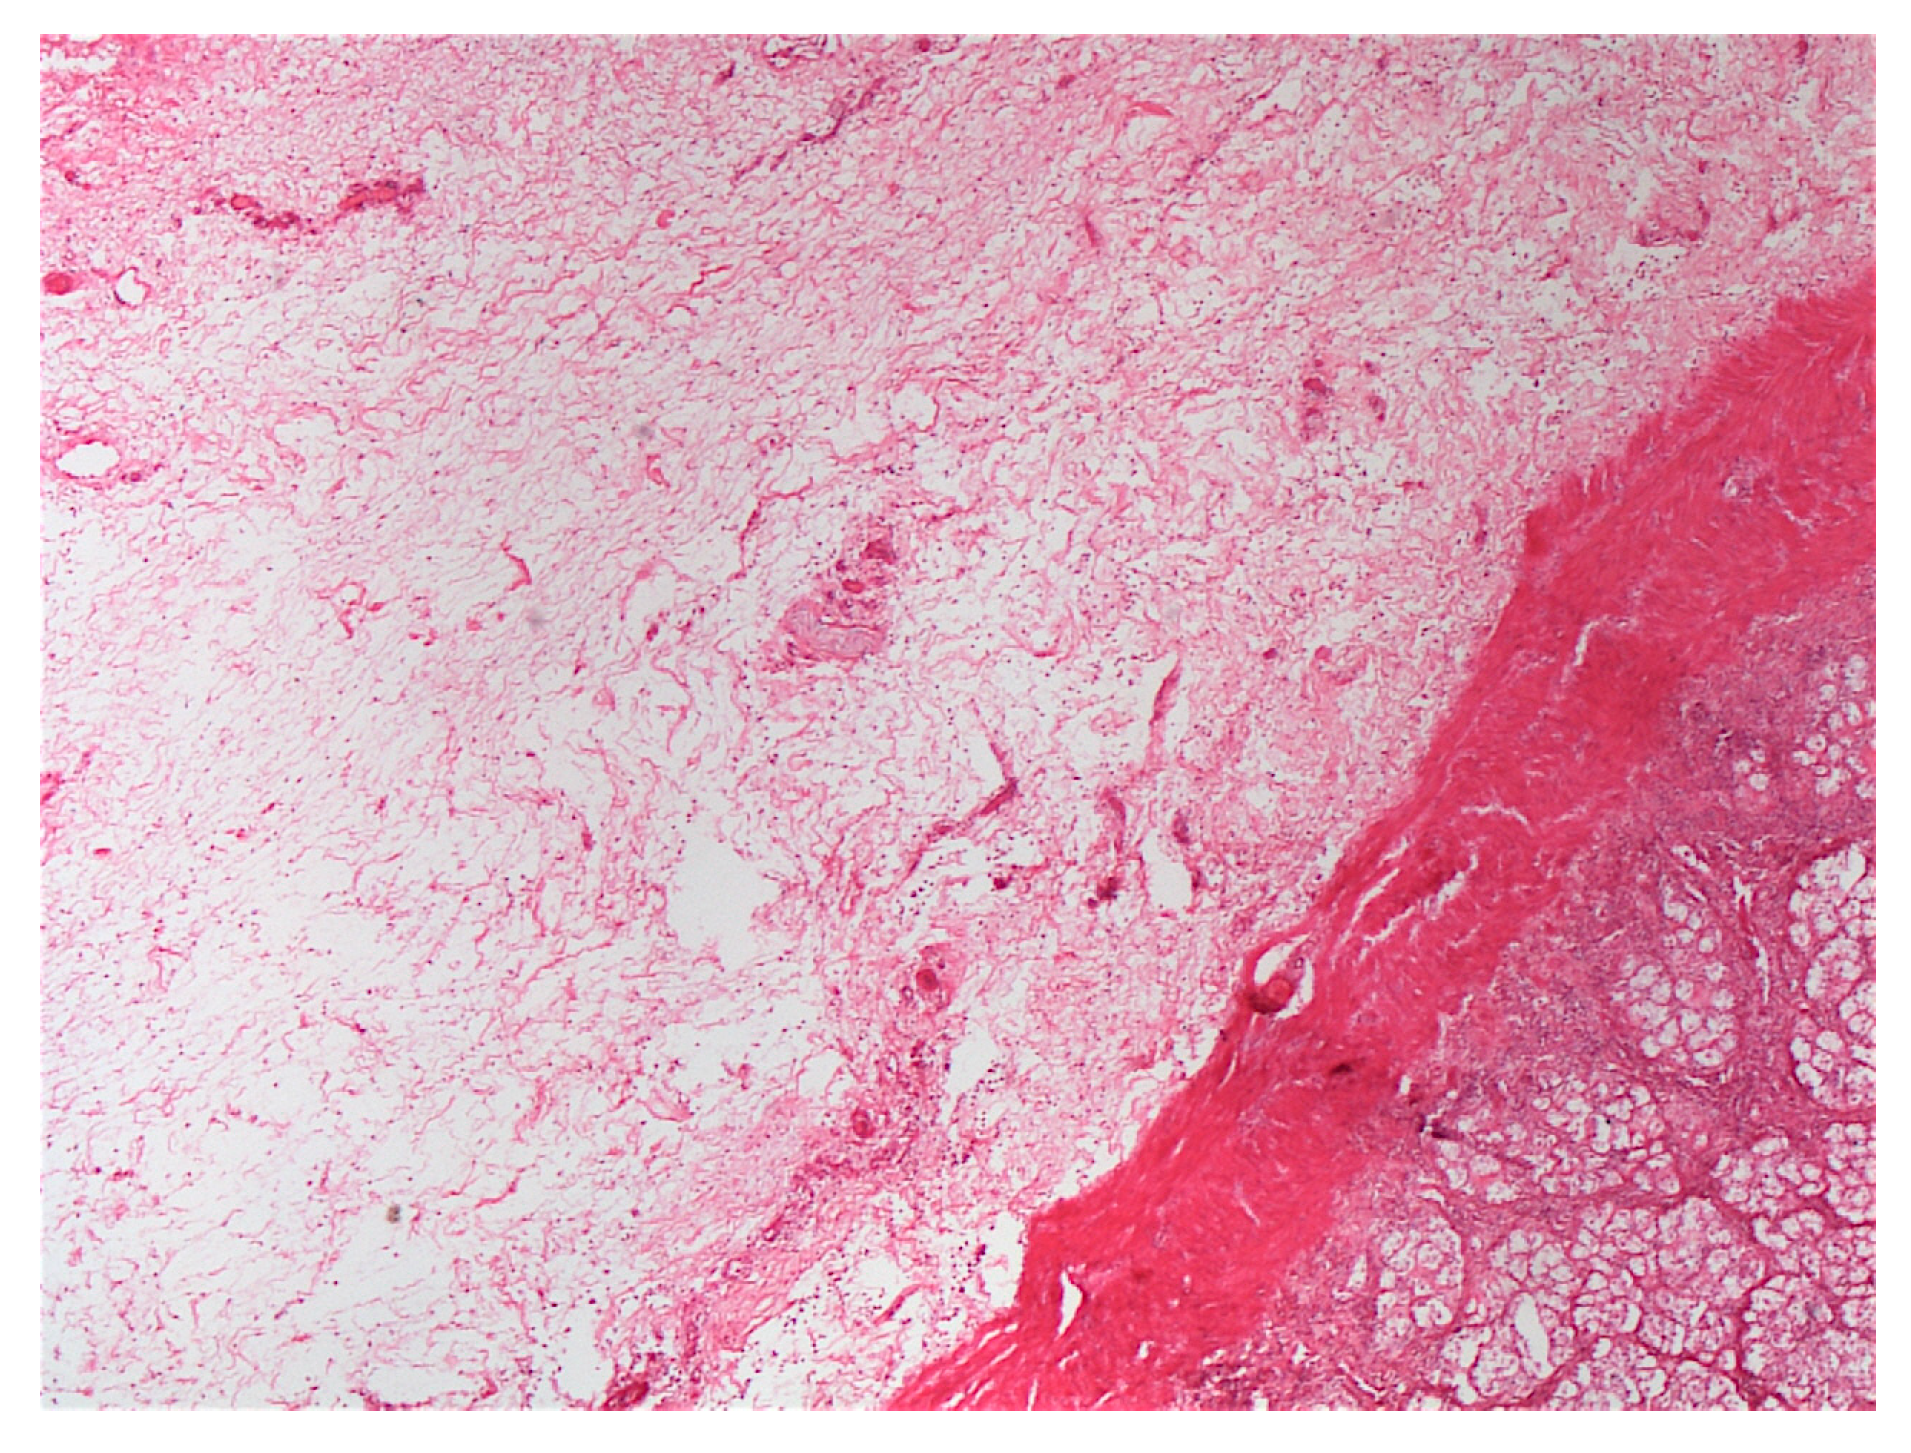

Post-mortem findings were available for five horses. A large amount of acorn husks (Figure 9) were observed in the intestinal tract of all horses (n = 5/5). Main lesions observed were an extensive severe edematous colitis in four of the five horses (Figure 10, Figure 11 and Figure 12). The cadaver of the last one was too putrefied for post-mortem examination. Extensive ulcers were present in two horses, while extensive hemorrhages appeared in two others. Other significant lesions included petechia, peritoneal or pleural effusion, renal congestion and adrenal hemorrhage.

Transversal section of ascending colon.

In addition to the marked seasonality, the clinical presentation was quite typical with an acute to fulminant severe edematous colitis leading to toxic shock, which was complicated in several cases with marked azotemia, increase hepatic or muscle enzymes, and intravascular hemolysis. Although not fully detailed in other studies, the hemato-biochemical results were similar to previous reports [,] and can be easily understood in view of the acute colitis shock. Abdominal ultrasonography examination revealed marked thickening of the large colon wall, especially in non-survivors with values rarely encountered in other diseases. The thickness was so severe that clear measurement was sometimes difficult (Figure 7). This reflects the severe colon edema as it could be observed post-mortem (Figure 11 and Figure 12).